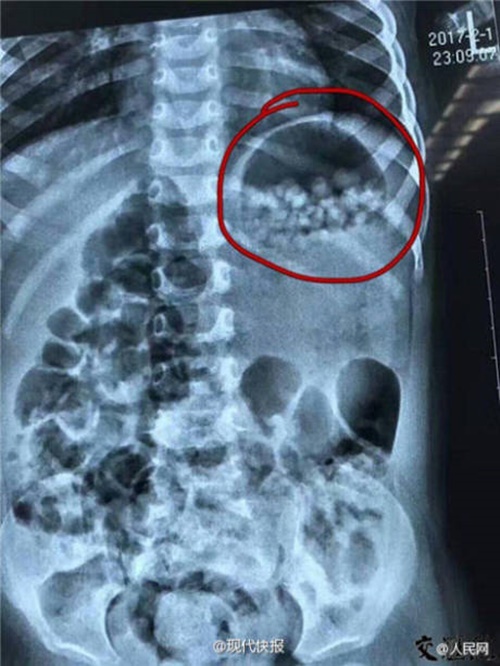

Vội vàng đưa con lao tới bệnh viện cấp cứu, cặp vợ chồng hốt hoảng kể lại sự việc cho bác sĩ. Sau khi chụp X-quang, các bác sĩ thấy trong bụng cô bé đã bị lấp đầy bởi các hạt nở nhỏ. May mà hai vợ chồng phản ứng nhanh, nên các hạt nở vẫn chưa nở bung ra trong dạ dày của cô bé.